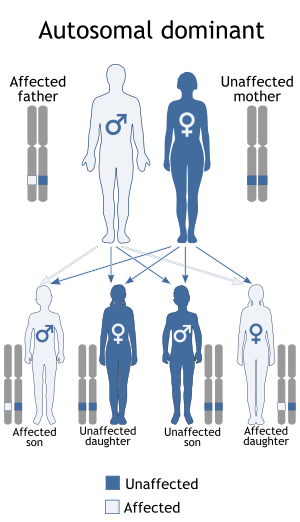

Gardner syndrome is inherited in an autosomal dominant manner.[2] Typically, one parent has Gardner syndrome. Each of their children, male and female alike, are at 50% risk of inheriting the gene for Gardner syndrome.